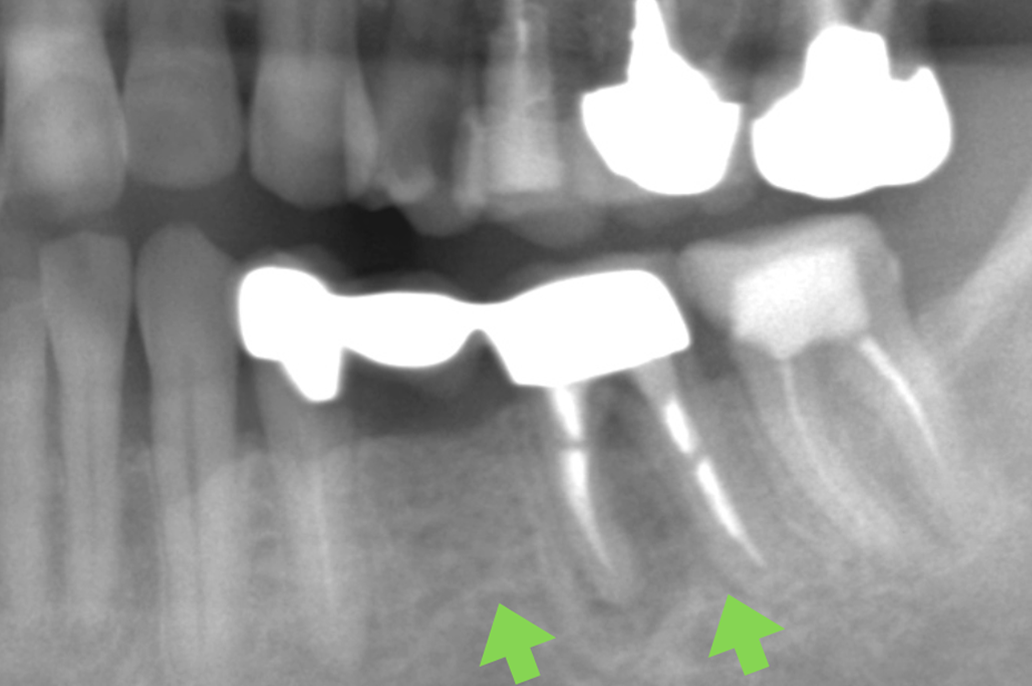

| 主 訴 | 30年前に治療した部分が心配、 全て綺麗に新しくしたい |

|---|---|

| 治療期間 | 約1年 |

| 治療費 | インプラント2本、 オールセラミッククラウン12本 2,420,000円(税込) |

| 治療内容 | 右上の奥歯2本をインプラントで治療を行いました。 残りの古い被せ物を全て除去し仮歯を作成、 その後セラミックの型取りを行い、 セラミックをセットしました。 |

| 治療のリスク | 仮歯の間は噛み合わせに違和感を感じる場合が あります。 セラミックは稀に欠ける場合があります。 |